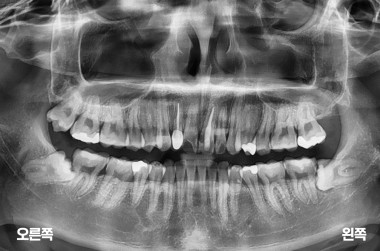

4

4개의 사랑니 발치